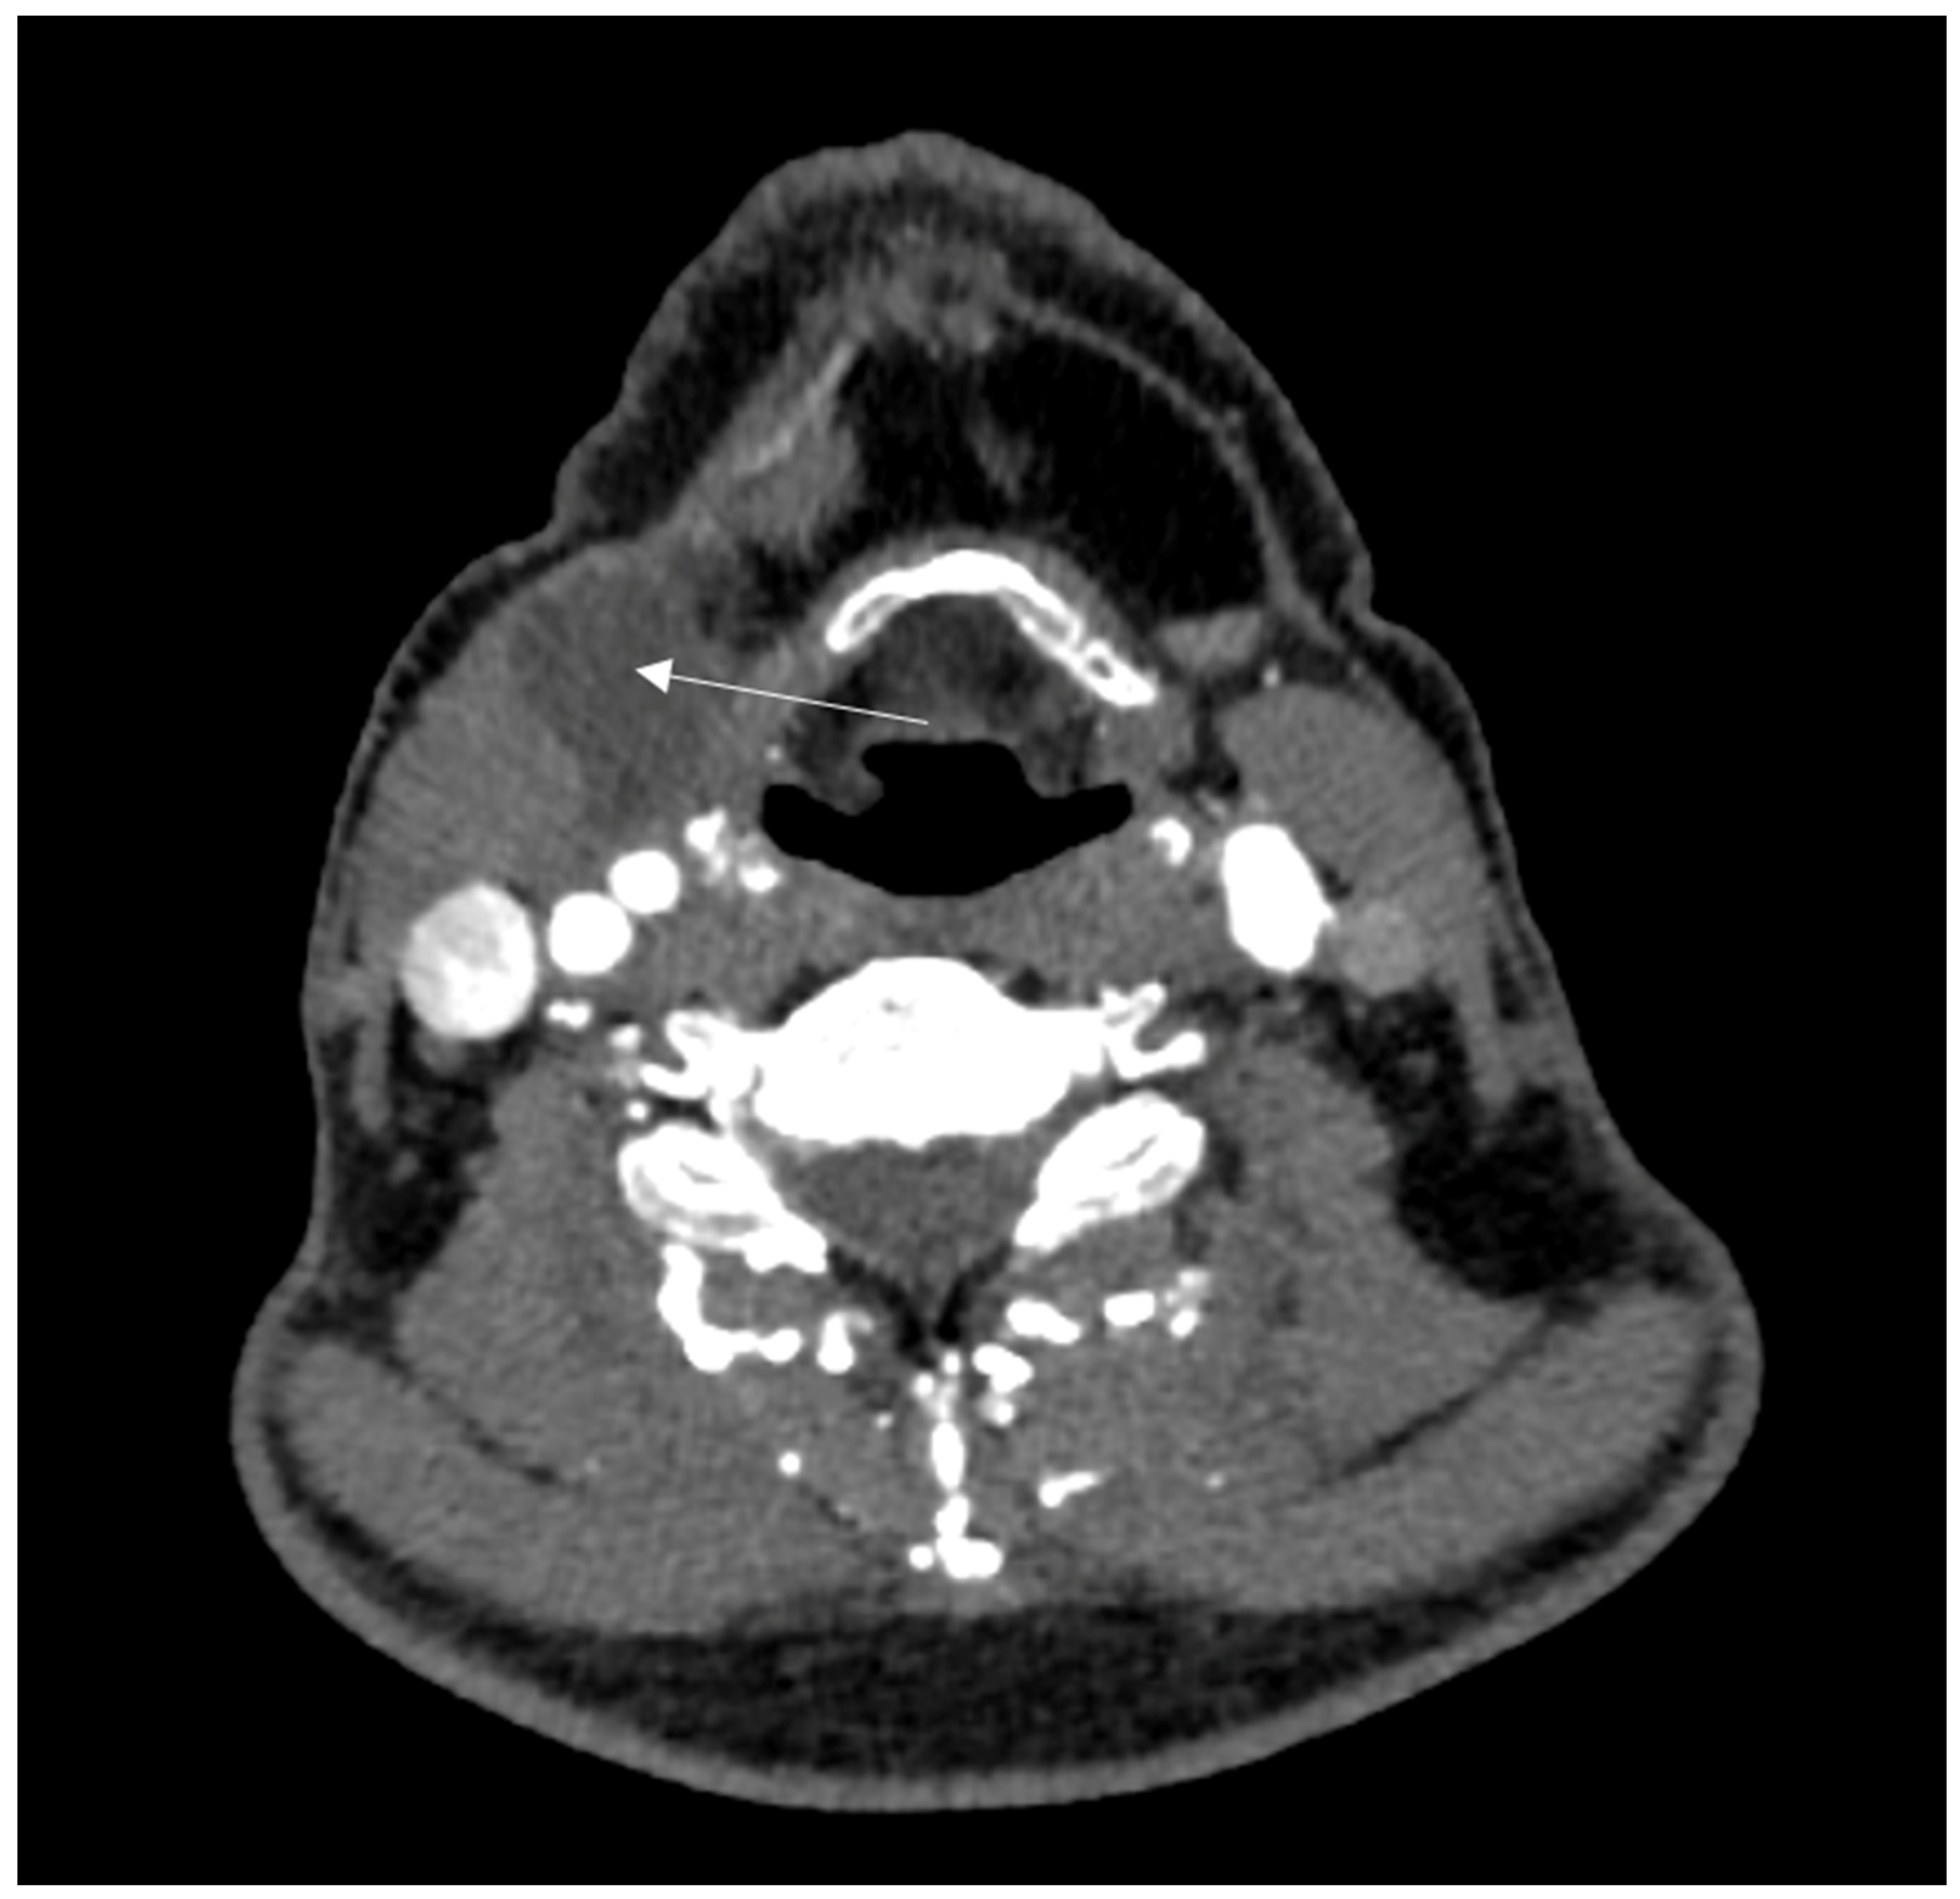

2. Case Report